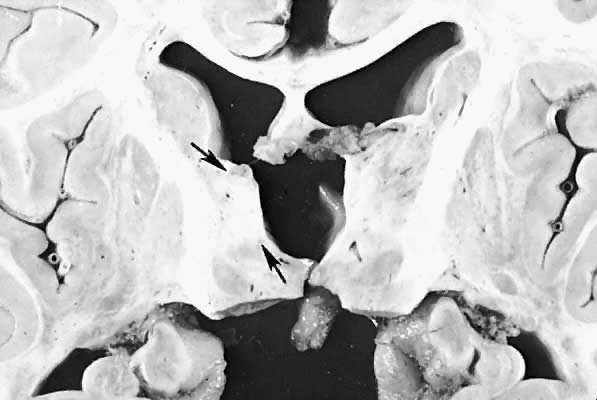

Five major neuropathologic patterns of injury are summarized in Table 2. Distribution of the lesions reflects a combination of regional circulation and metabolic factors that change with the gestational age of the infant. Both the degree of myelination and the presence of excitatory amino acid binding sites also may play a role in the pathophysiology of tissue damage.6 The primary lesions seen on autopsy in term newborns are in the cortex and basal ganglia (Fig. 1). In the premature infant, however, lesions generally occur in the germinal matrix and periventricular regions of the brain (Fig. 2). Efforts to resuscitate the infant should be directed toward adequate ventilation and perfusion, correction of accompanying metabolic acidosis, maintenance of normal blood pressure and glucose, and treatment of seizures. Antidiuretic hormone may be secreted inappropriately after a large cerebral insult, and fluid overload should be avoided. Serum osmolarity and sodium concentration should be monitored to avoid the consequence of cerebral edema and seizures. Although antiedema agents may reduce intracranial pressure, it is unclear whether they improve long-term neurologic sequelae.4 Seizures in the hypoxic-ischemic setting may be refractory to anticonvulsant therapy, but treatment is recommended to reduce the incidence of apnea and hypertension. Handling should be minimized to reduce the incidence of hypoxemic episodes, especially in the premature neonates.

Fig. 1. Status marmoratus of basal ganglia. Arrows indicate shrinkage of basal ganglia and glial scar.

Fig. 2. Periventricular leukomalacia. Note discoloration and fragmentation of subependymal white matter ( arrows ).(Courtesy of Dr. M. Barmada.)